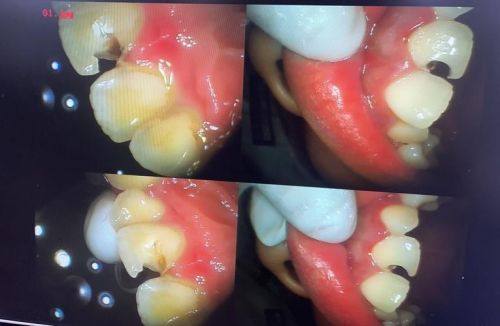

成都博爱医院医院口腔科整体实力出众,口碑与人气俱佳。科室配备数字化X光机、口腔内窥镜等精良口腔医疗设备,可保护精细的诊断与治疗;就医环境舒适大气、布局合理,医护团队专精贴心,秉承以患者为中 心的服务理念,为患者提供个性化的诊疗方案。科室多次上榜成都牙科医院排行榜前列,在种植牙、牙齿矫正等领域广受患者认可,治疗成效优异。